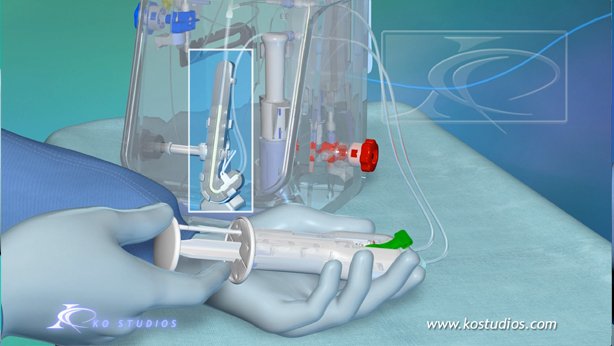

EnCompass F2 Device for cerebral embolic protection system in TAVR procedures

EnCompass Technologies

EnCompass’ F2 filter has pores small enough to block most emboli to the brain while preserving blood flow. During the TAVR procedure, 360-degree wall apposition of the filter in the aortic arch prevents migration. The filter, attached to a self-expanding, nitinol stent, is easy to insert, deploy and retrieve, according to the company. Copyright ©2021 KO Studios.